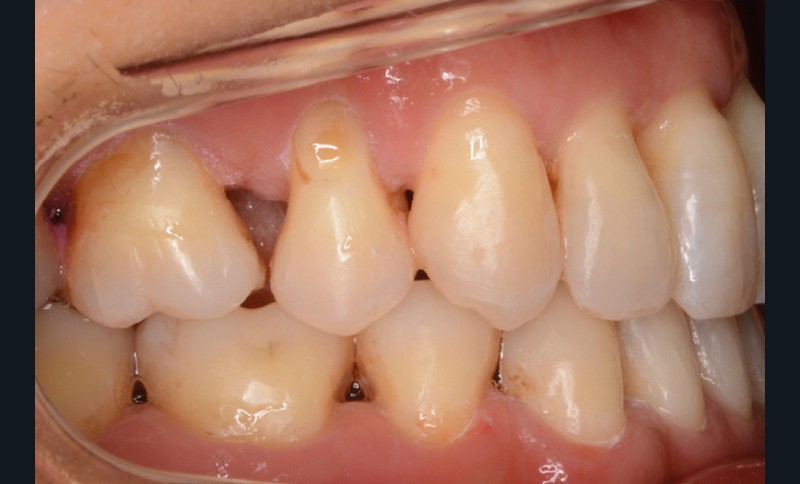

La patiente présente par ailleurs une parodontite chronique modérée stabilisée (Stade 3, grade C selon la classficaiton de Chicago 2018) et bénéficie d’une maintenance trimestrielle chez son parodontiste, qui nous donne son accord pour le traitement orthodontique moyennant un suivi très régulier.

Sur le plan dentaire, la patiente est en classe III droite et gauche, canine et molaire de 6 mm, avec une occlusion inversée antérieure localisée à 11, 12 et 22. Elle présente une dysharmonie dents-arcades sévère, une agénésie d’une incisive mandibulaire est à signaler, et les troisièmes molaires ont été extraites à l’âge de 21 ans.

Au niveau fonctionnel, on note un bruxisme statique avec contact permanent entre les dents maxillaires et mandibulaires. La patiente présente des prématurités en relation centrée sur les incisives, le guidage en propulsion est perturbé et des interférences multiples sont retrouvées en latéralités droite et gauche.